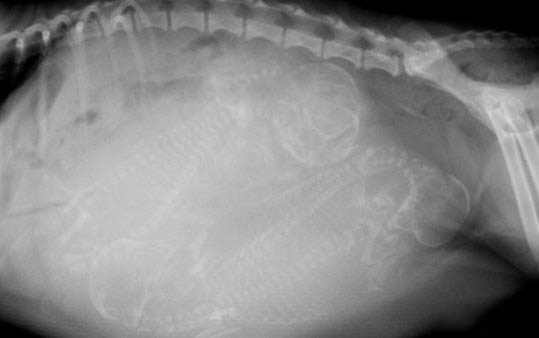

狗狗得了腎病后會(huì)表現(xiàn)出腹水、水腫、嘔吐以及腹瀉等病癥,如果病情比較嚴(yán)重還會(huì)出現(xiàn)尿失禁、脫水,甚至還會(huì)影響其他健康的器官。當(dāng)然狗狗得了腎病,具體所表現(xiàn)的癥狀也要結(jié)合腎病的類型來決定,腎病當(dāng)中還包括腎小球以及腎炎等。病型不同所表現(xiàn)的不適癥狀,也會(huì)有所差異。